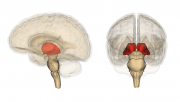

| 00:10, 4 June 2019 | Thalamus image.png (file) |  |

313 KB | Lisa (talk | contribs) | 1 | |